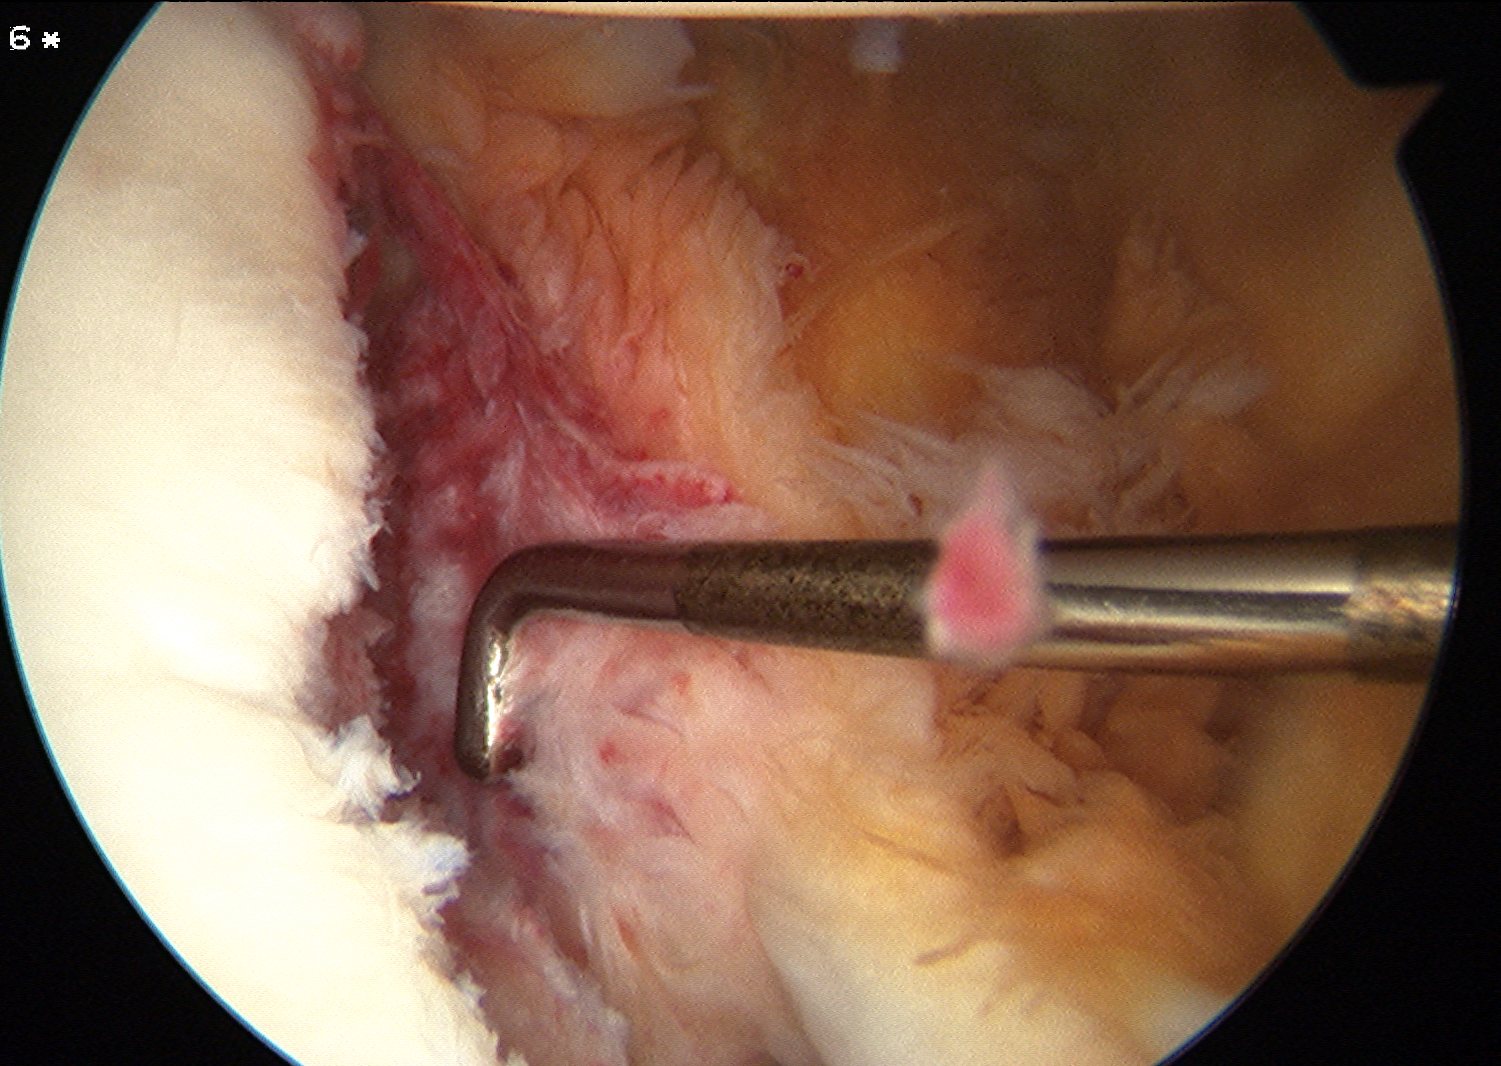

Mobilize labrum

Labral mobiliser / rasp

- labral tear can be obvious, but may have partially healed or healed medially

- change camera to anterosuperior portal for better view

- mobilize until can see subscapularis muscle underneath

- need to be able to advance labrum medially and superiorly for repair